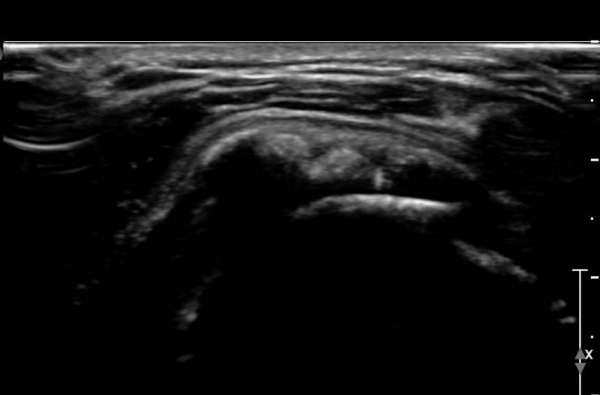

±Ø»ó°Ç Á¾´Ü¸é°Ë»ç»ó ±Ø»ó°Ç ¾Õ(»çÁø 4), Áß°£(»çÁø 5), ÈĹæ(»çÁø 7)¿¡ ±¤¹üÀ§ÇÏ°Ô ¼®È¸¸¦ º¸À̰í

Ⱦ´Ü¸é°Ë»ç(»çÁø 6)¿¡¼­µµ ±Ø»ó°Ç ³»ÃøºÎÅÍ ¿ÜÃø±îÁö ±¤¹üÀ§ÇÑ ¼®È¸°¡ °üÂûµÈ´Ù.

ÃÊÀ½ÆÄ À¯µµÇÏ¿¡ ÁÖ»ç±âÀ» ÀÌ¿ëÇÏ¿© ¹Ýº¹ÀûÀÎ ÀÚ±Ø(needling)ÈÄ Á¡¾×³¶´ë ÁÖ»çÀ» ½ÃÇàÇÏ¿© ¼®È¸¸¦

Ä¡·á ÇÒ ¼ö Àִµ¥(÷ºÎµ¿¿µ»ó 2) ÀÌ·± ¹æ¹ýÀº ÀÛÀº ¼®È¸È­ Ä¡·á¿¡ À¯¿ëÇÏ´Ù.

¼®È¸°¡ Å©°í ´Ü´ÜÇÑ °æ¿ì¿¡´Â ¼®È¸¸¦ ±ú´Â Ä¡·á¸¦ ½ÃÇàÇØ¾ßÇϴµ¥ ±¹¼Ò¸¶Ã븦 ½ÃÇàÇÏ°í ¼®È¸³»¿¡

ÁÖ»ç¿Í ÈíÀÎÀ» ¹Ýº¹ÇÏ´Â ¹æ¹ýÀ¸·Î ½ÃÇàÇÑ´Ù. ÷ºÎµ¿¿µ»ó 3¿¡¼­ º¸µíÀÌ ¹Ýº¹ÀûÀÎ ÁÖ»ç¿Í ÈíÀÎÀ¸·Î

´Ü´ÜÇÑ ¼®È¸°¡ Âɰ³Áö´Â °ÍÀ» º¼ ¼ö ÀÖ´Ù.